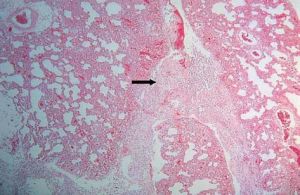

1.典型異物反應為巨噬細胞及異物巨細胞包圍異物,細胞質內可見有吞噬的異物,尚可見異物如縫線、液狀石蠟油、矽鹽毛髮等均可引起異物反應。

2.異物過敏反應,可出現上皮樣細胞構成的結核樣結節,具有巨細胞及乾酪樣壞死,但缺乏或少有吞噬異物現象鈷鈹或紋身顏料可引起異物過敏反應。

3.一些特異性異物肉芽腫,如紋身肉芽腫可見顏料顆粒矽肉芽腫為非結核性肉芽腫為多數巨噬細胞和多核細胞的炎症浸潤,可見折光性強的針狀矽結晶。